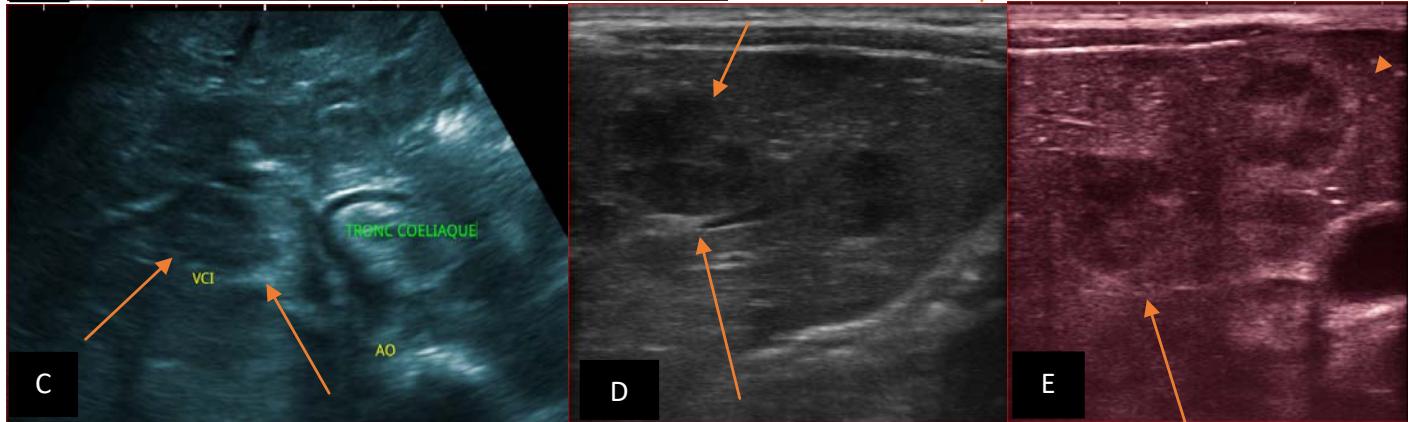

Figure 5: Abdominopelvic ultrasound control after 6 courses of chemotherapy in the same 3 year old patient with a ruptured left renal nephroblastoma; Images A, F, G, and H: show regression of the solid, endo and exo renal, left nephroblastoma mass treated with 6 courses of chemotherapy (current volume 430 ml vs) Images: B, C, and: show persistence of thrombotic permeation pan vena cava and ipsilateral renal. Image E: shows a volumetric regression of the intra-lesional hematic collection, at the tumor rupture estimated at 34.49 ml VS, Image I: represents the right kidney in B mode which is of normal echoculture. Source: Dr. Frederick Tshibasu Tshienda database.